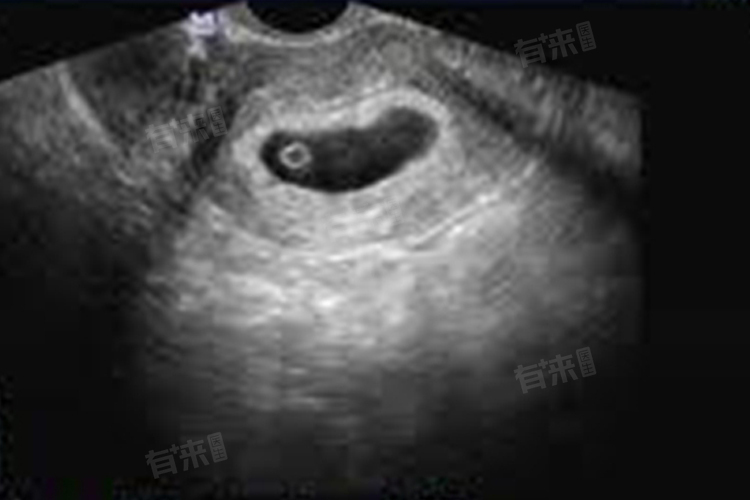

- 孕囊是怀孕初期形成的原始胚胎组织,包含了胎芽和胎心等重要的胚胎结构。在怀孕初期,孕囊的大小会随着孕周的增加而逐渐增大。当孕期达到47天时,孕囊已经发育到了一定的规模,可以通过B超检查清晰地观察到。

- 具体来说,怀孕47天的孕囊大小平均为2厘米,或者接近17-18毫米。这个大小范围是根据大量临床数据和B超检查结果得出的平均值,但需要注意的是,由于每个女性的月经周期、排卵时间以及受精卵着床时间都存在差异,因此孕囊的实际大小可能会有所不同。

- 除了孕囊的大小外,医生还会关注孕囊的形态、是否规整、是否饱满,以及囊内胎芽和胎心的发育情况。在怀孕47天时,孕囊内通常已经可以看到胎芽的出现,胎芽的大小一般几毫米左右,接近或稍小于孕囊的大小。同时,胎心也开始出现微弱的搏动,这是胚胎发育的重要标志之一。